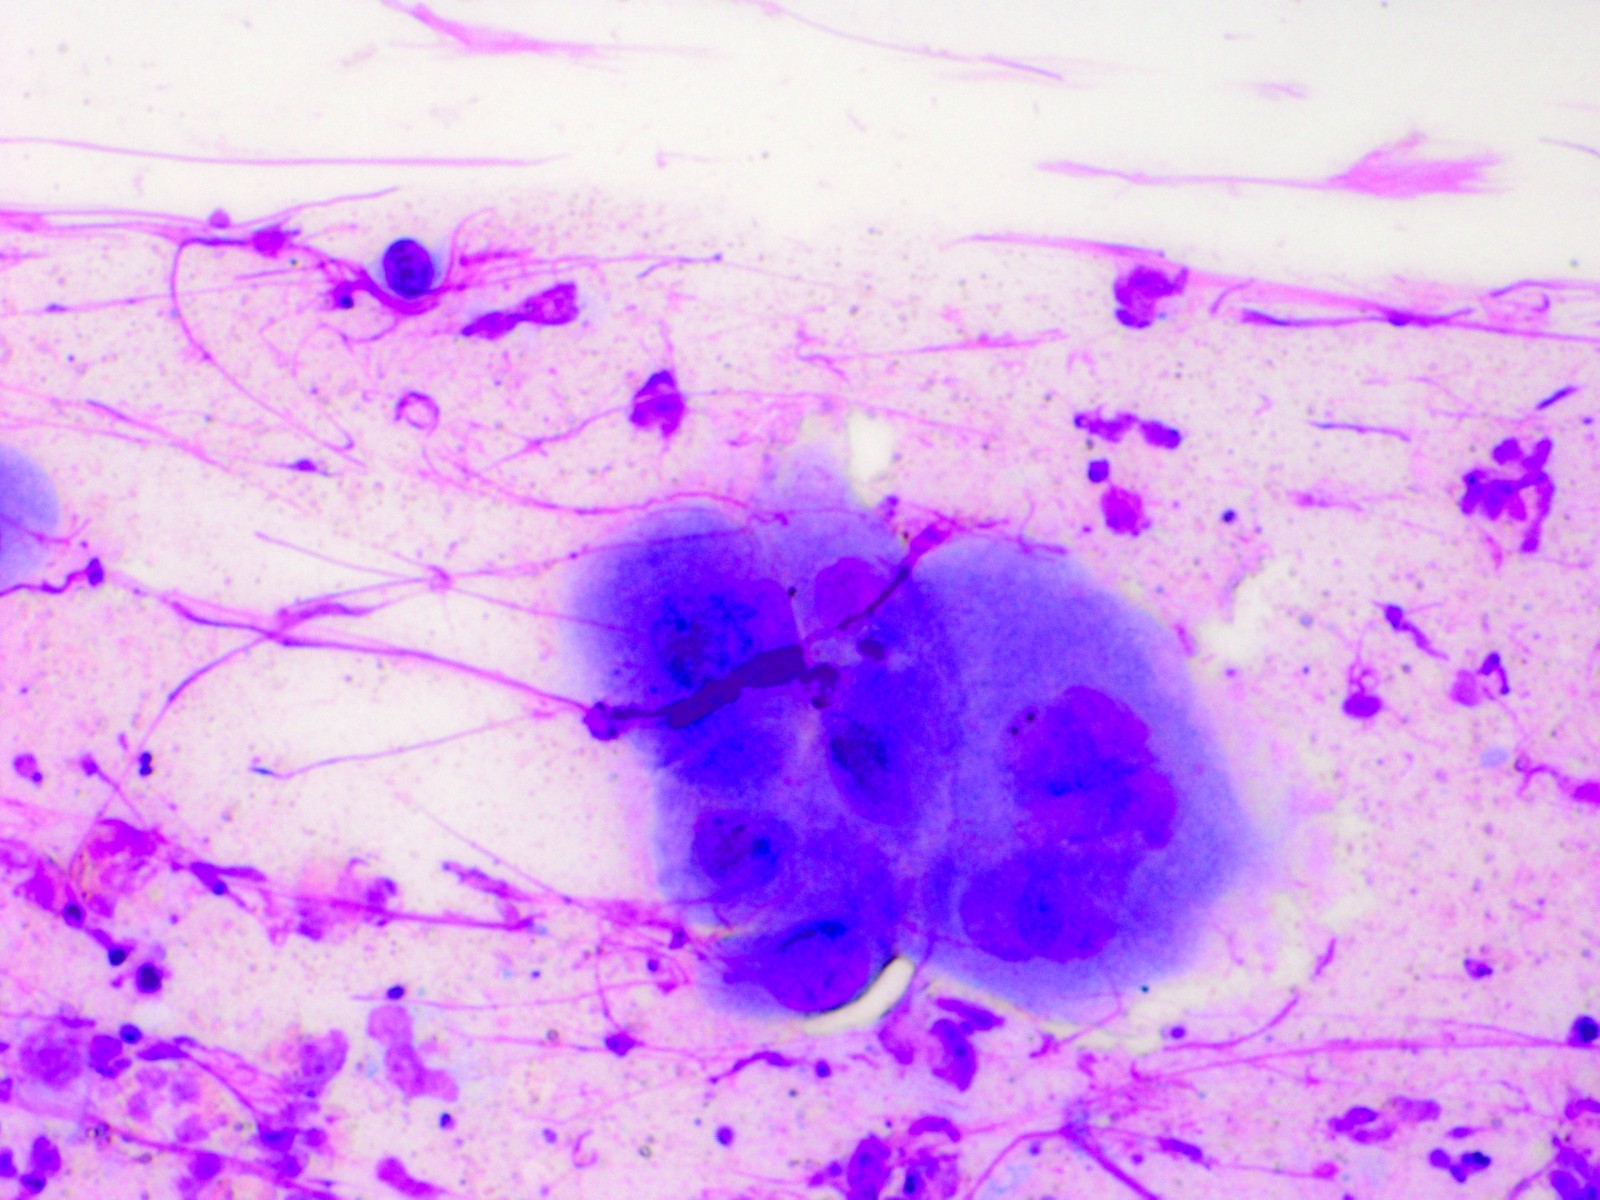

Tzanck test met multinucleate giant cells Tzanck test met multinucleate giant cells

Tzanck test (reuscellen) Tzanck test (reuscellen)

De epidermis toont holtevorming door degeneratie van epitheelcellen. Twee typen degeneratie komen voor, namelijk balloniserende en reticulaire. De balloniserende degeneratie is gekenmerkt door opzwelling van de cellen, die vaak een homogeen, eosinofiel cytoplasma tonen; de kern verdwijnt later. In deze kernen kunnen de insluitlichaampjes van Lipschutz te zien zijn. Deze komen zowel voor bij herpes simplex als bij Varicella en Herpes zoster. Zij bestaan uit kernsubstantie resten die nagenoeg geen viruspartikels meer bevatten. De lichaampjes van Lipschutz zijn eosinofiel; vaak zijn zij omgeven door een heldere zone (halo). In de vesikelbodem komen door confluering meerkernige balloon cellen voor. De reticulaire degeneratie ontstaat door zwelling en vervloeiing van de cellen; resten van de celwanden blijven over en tonen een reticulair patroon. Door samensmelten van de holten in de epidermis lijkt het blaasje in latere stadia subepidermaal te liggen. Deze veranderingen komen zowel voor in de epidermis als in de adnexen (haarfollikel, talgklier). Door uitstrijken van blaasjesbodem en kleuring volgens Giemsa (Tzanck test) is het soms mogelijk de typische meerkernige cellen of cellen met insluitlichaampjes rechtstreeks waar te nemen. In het bovenste gedeelte van de cutis bevindt zich een aspecifieke ontsteking met lymfocyten en enkele polynucleaire granulocyten. Soms is het ontstekingsbeeld zeer heftig, met verschijnselen van een gelokaliseerde leukocytoclastische vasculitis.